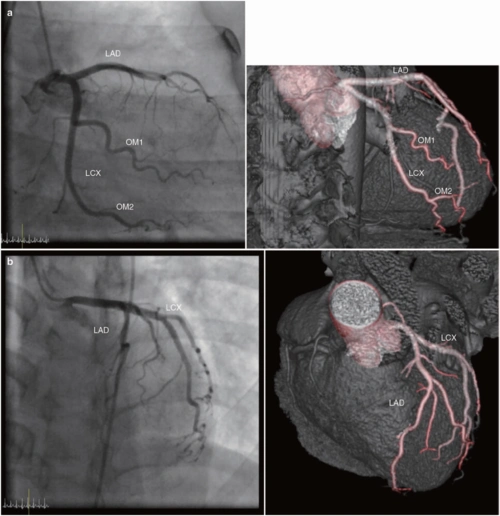

ct和mri如何看正常及异常冠状动脉,高清图谱请收好!

ct如何看冠状动脉狭窄高清图谱详解要点

心脏冠状动脉ct解剖中文详细标注(图文).